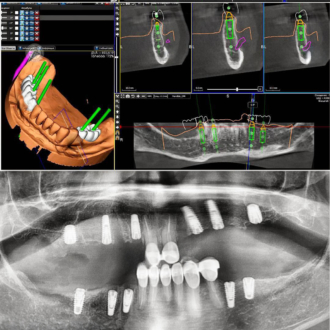

- виконання рентгенограми та КТ запланованого місця імплантації для визначення щільності щелепної кістки, ступеня її атрофії, наявності можливих патологічних вогнищ

- планування етапів імплантації та моделювання зовнішнього вигляду майбутнього зубного ряду

Хірургічний етап проходить під місцевою анестезією або в умовах медикаментозного сну. Після надрізу ясен і оголення щелепної кістки в місці імплантації стоматолог виконує остеотомію (отвір для імплантату) за допомогою свердел різного діаметра, поступово розширюючи місце імплантації. Остаточний остеотомічний отвір відповідає товщині та довжині імплантату, який буде в нього встановлений. Імплантат фіксується у кістці, після чого відбувається ушивання зони втручання.